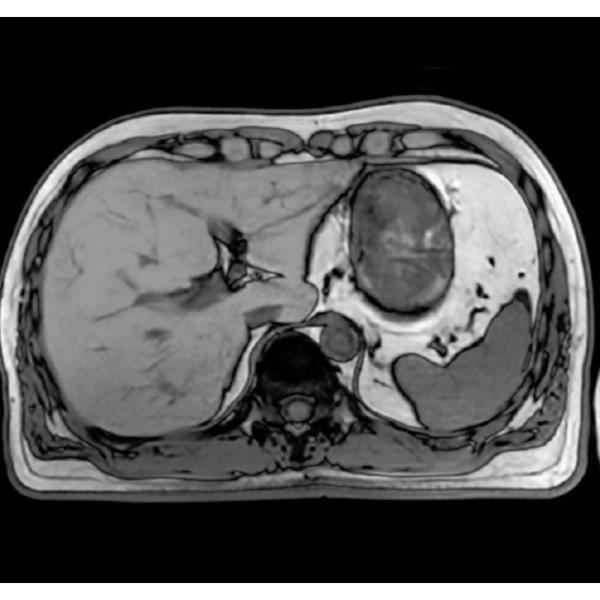

"DLR" is applicable to all body parts and promotes high speed imaging and diagnostic efficiency

IP-RAPID x DLR Plus can also shorten imaging time, allowing more images to be taken in the same examination time.

Additional imaging, such as different image types and cross sections, can be added to the conventional examination to increase the amount of information and make the diagnosis more reliable.

IP-RAPID x DLR Plus gives you the flexibility to shorten respiratory gated series or even replace them with breath-holds, depending on the patient’s situation. This gives you more options and a wider range of examinations to choose from.

IP-RAPID x DLR Plus can be used for basic imaging such as VolumeScan, RadialScan, HalfScan, and many other imaging methods such as MultiContrastScan FatSep and DWI.

It can also be used with time-consuming scans such as Whole Body DWI and Whole Spine imaging, providing more detailed information in many areas than previously possible.